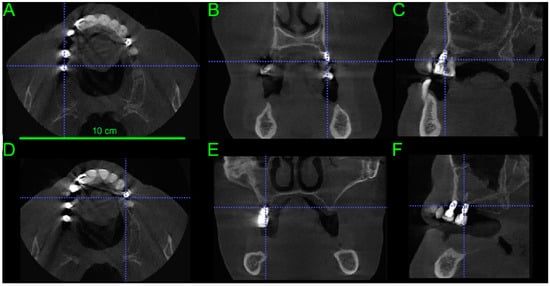

3. Results